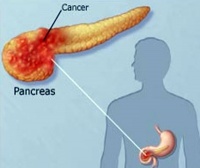

胰腺结石可分为两种类型:一种是主胰管结石,另一种是胰小管内钙化石。前者称之为真性结石,后者为假性结石。结石的大小不等,大者呈巨块状,可达100~200g,主要嵌在胰管内,小者仅能辨认。结石的形状为多样性:卵圆形、球形、分枝形、三角形等。

胰腺结石长期存留则刺激胰腺管上皮细胞,使之肥大增生,继而发生鳞状上皮化生。并使胰管狭窄、阻塞。在早期胰腺周围水肿、胰腺肿胀,及至晚期一方面由于胰管的阻塞,另一方面由于胰腺的纤维化,则导致胰腺明显受损,表现为胰腺的全部或大部萎缩、塌陷、变硬,切面呈白色出血较少。有时由于胰管的阻塞可伴发胰腺囊肿或脓肿。纤维化的组织可将胰岛包绕、收缩而影响其功能——发生糖尿病。在鳞状上皮化生的基础上则可能发生癌变。

由于胰腺结石导致的胰腺损害较为明显,故易于引起一系列的并发症,如糖尿病、胰腺癌等。最常见的并发症有下列几方面。

3.恶性并发症:胰石症的恶性并发症一种是胰腺本身,另一种为胰腺以外的恶性肿瘤。胰石症与胰腺癌的关系极为密切。一般是胰结石在先而后发生胰癌。并发胰腺癌者多为大结石。约半数为胰头部。合并胰腺癌的发病率各家报道不一。欧美文献记载为3.6~25%,日本小口寿夫报道例胰结石并发胰腺癌31例(占14.8%)。日本的一般报道为5.3%~10%。